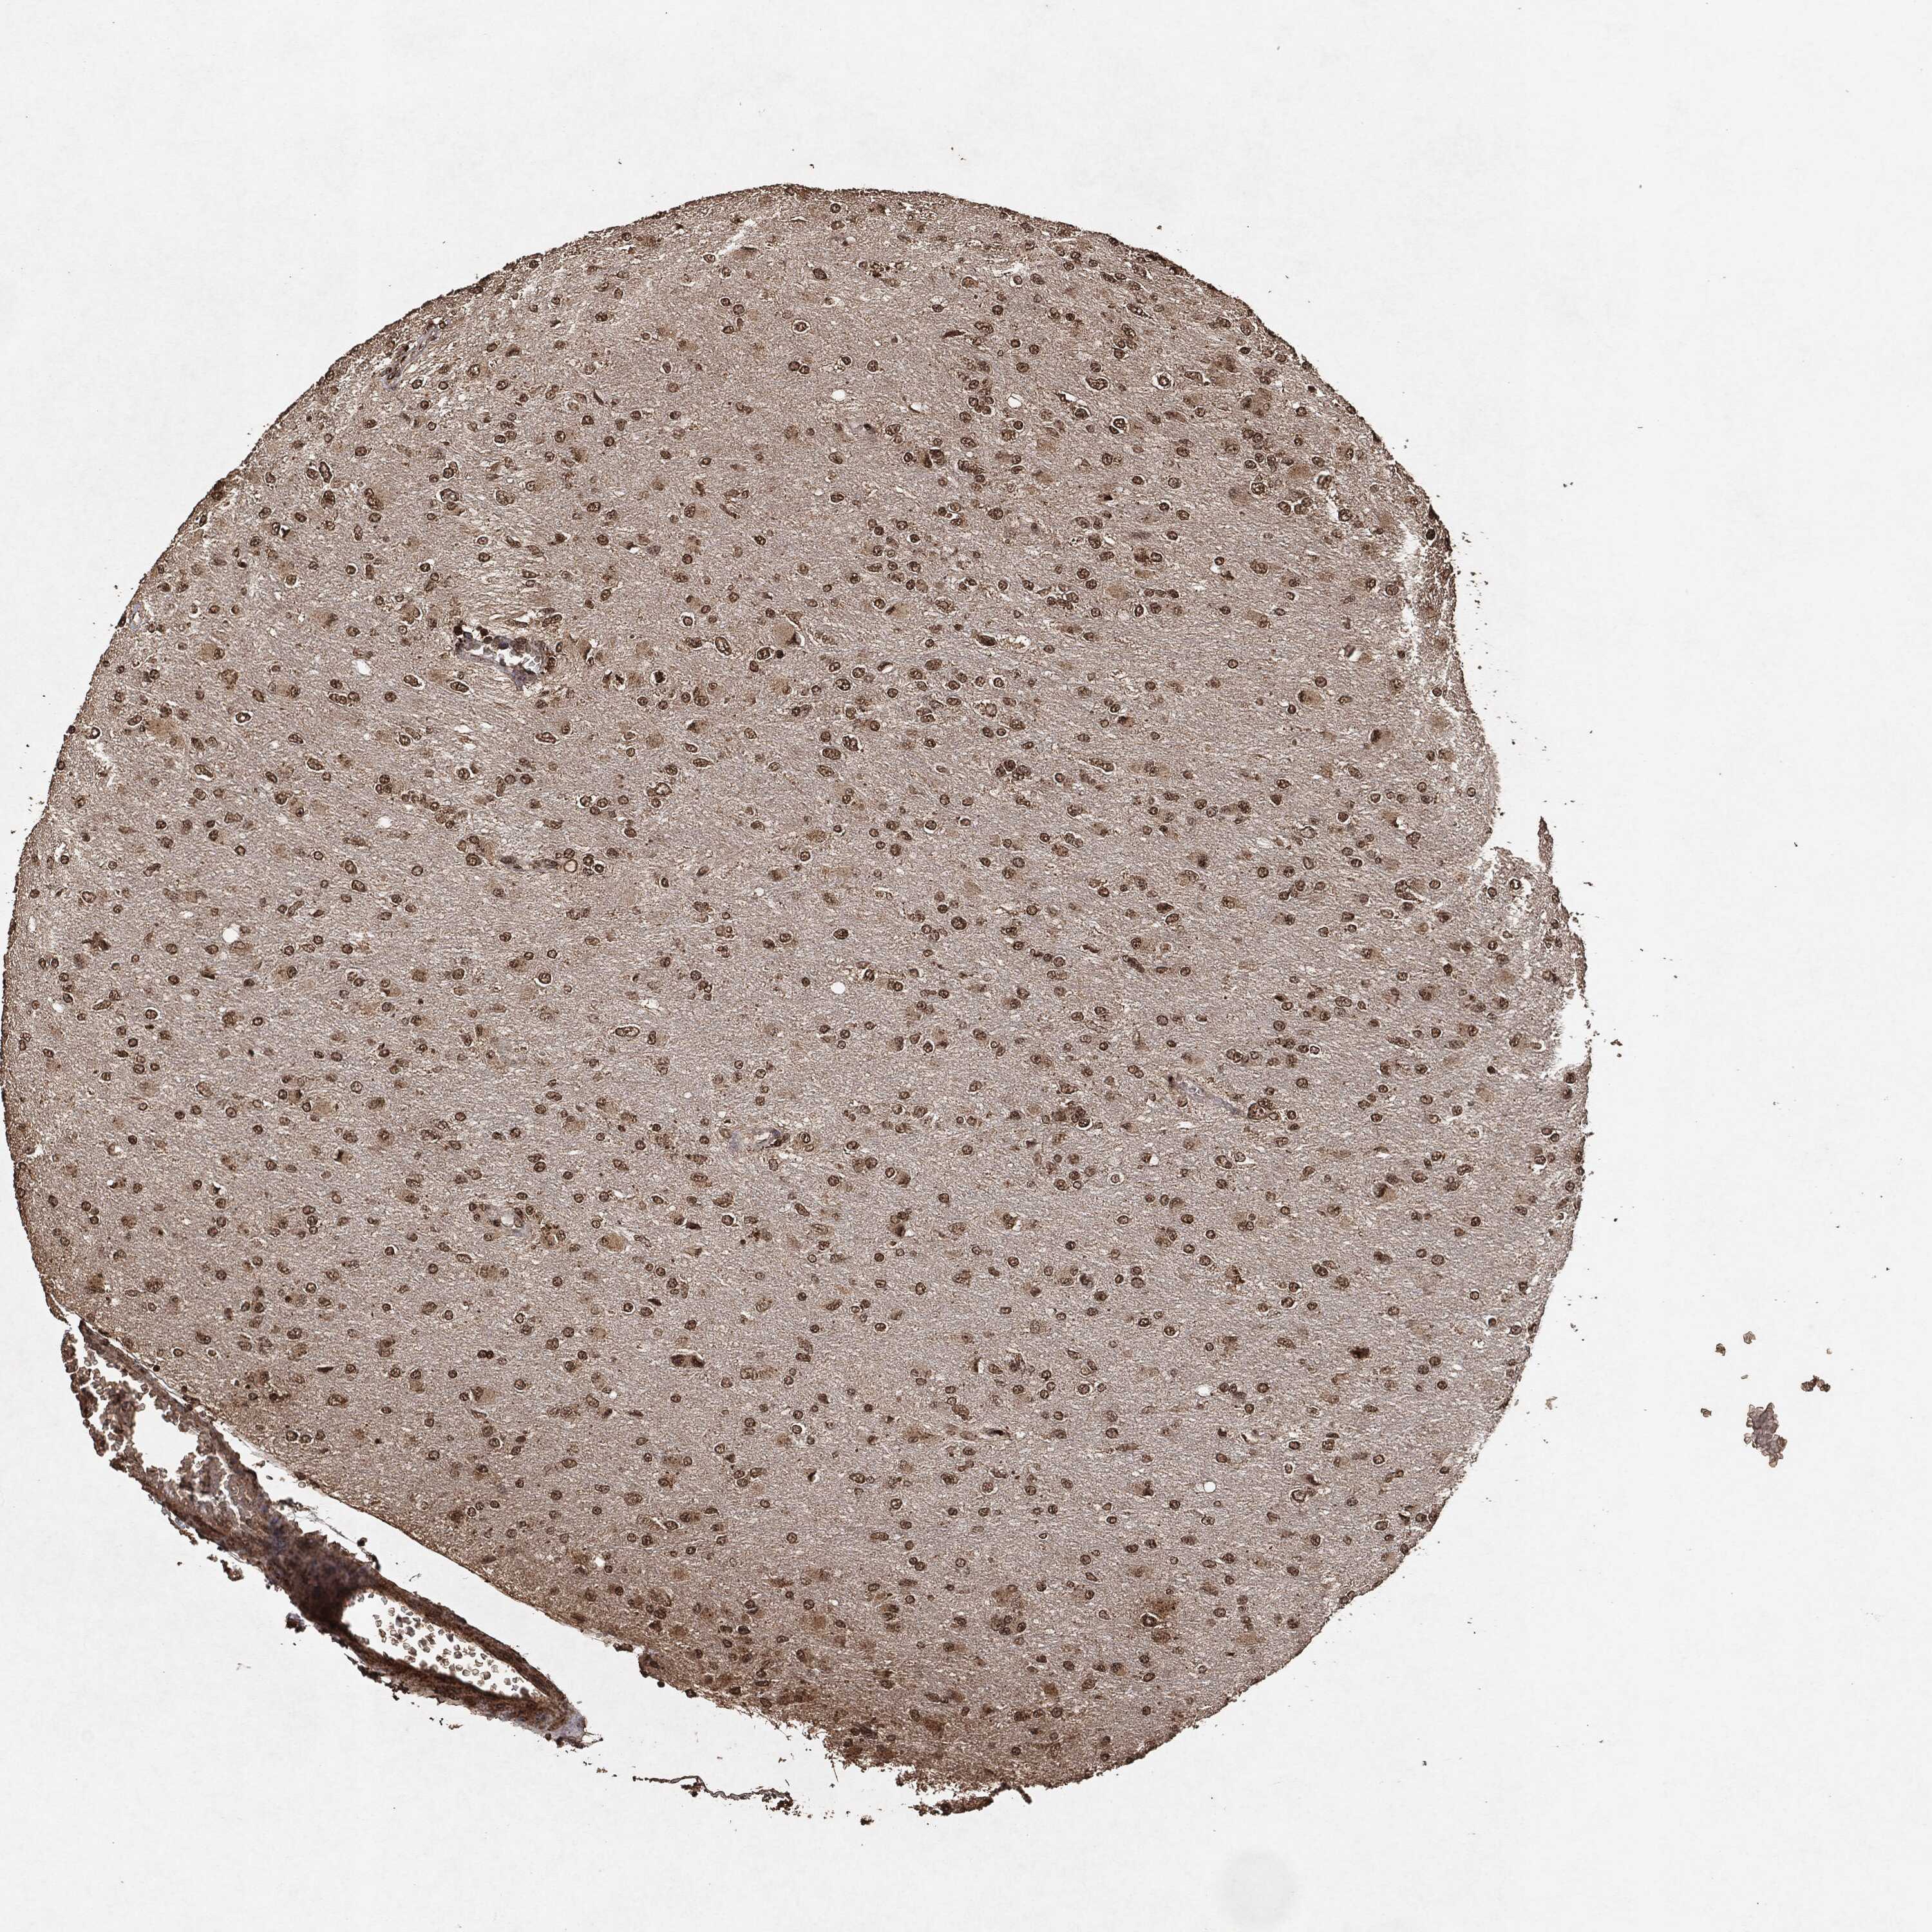

GLIOMA - Protein expressioni

A mouse-over function shows sample information and annotation data. Click on an image to view it in a full screen mode. Samples can be filtered based on level of antibody staining by selecting one or several of the following categories: high, medium, low and not detected. The assay and annotation is described here.

Note that samples used for immunohistochemistry by the Human Protein Atlas do not correspond to samples in the TCGA dataset.

Antibody stainingi

Antibody staining in the annotated cell types in the current human tissue is reported as not detected, low, medium, or high, based on conventional immunohistochemistry profiling in selected tissues. This score is based on the combination of the staining intensity and fraction of stained cells.

Each image is clickable and will lead to virtual microscopy that enables deeper exploration of all samples and also displays staining intensity scores, fraction scores and subcellular localization as well as patient and tissue information for each sample.

Glioma, malignant, High grade

Glioma, malignant, Low grade

Glioma, malignant, NOS